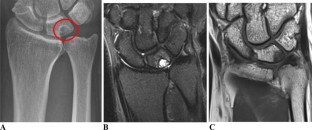

Fig. 3